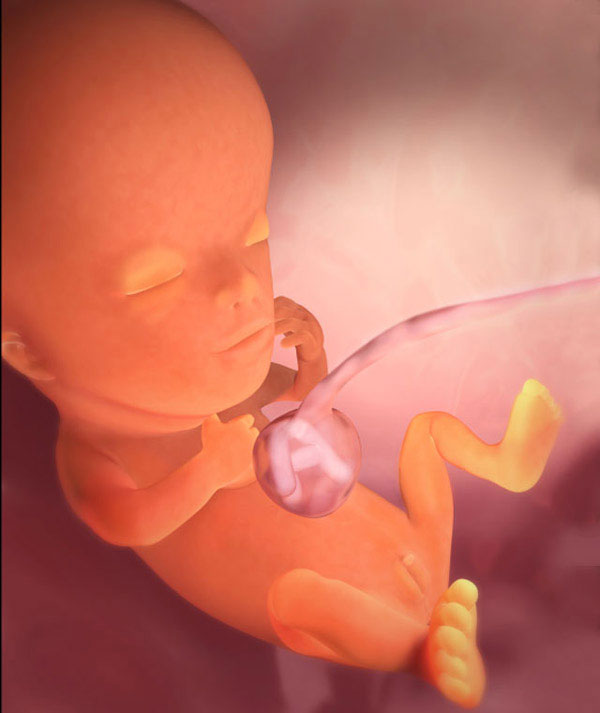

Tak wygląda płód w 11 tygodniu (klikalny):

USG w 11 tygodniu pokaże wyraźnie zarysy małego człowieka. Na wysokiej klasy sprzęcie ze szczególnie dobrą lokalizacją dziecka możesz już określić jego płeć. Jednak dane mogą być niedokładne.